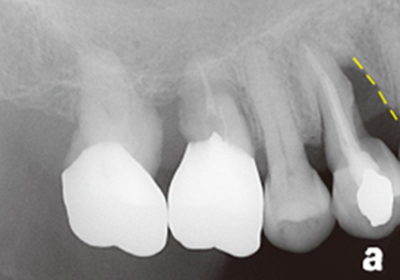

案例2

補骨前

補骨後